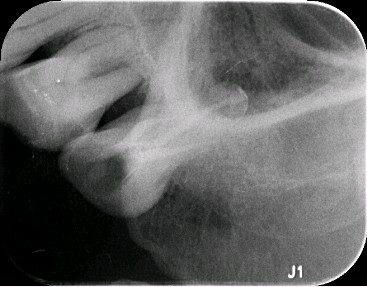

术中拔出的完整“牙神经”(牙髓)

术后根充片